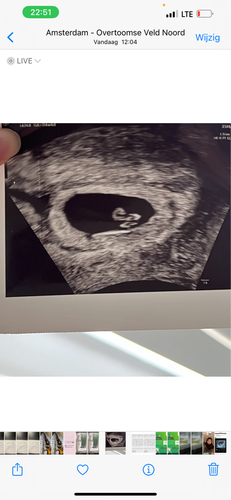

Was de echo inwendig?

Ik weet het niet zeker hoor maar omdat jou beebje juist aan de andere kant zit denk ik dat😅

Ik moet wel zeggen dat mijn echo er met 6 weken anders uit zag..

Ze zeggen dat de placenta in de buurt van het embryo is , dus neig dan meer meisje . Maar ik weet het niet hoor